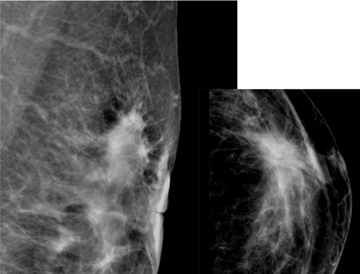

The aim of this research is to describe the intrinsic subtypes of breast cancer which has an appearance of spiculated mass on mammography. There were 59 patients that met the inclusion criterions at DR. Soetomo General Hospital, Surabaya between January 2017 and December 2018 (Figure 1−4). The youngest subject is 34 years old and the oldest being 73 years old with the average age of 52.1 years old. We divided the patients into three age groups, below 40 years old, 40-50 years old and above 50 years old. The average age of subtype Luminal A were the oldest with 53.6 years old, 52.9 years old in Luminal B, 47.4 years old in the basal-like and the youngest of which 46.8 years old in the HER2+subtype (Table 1) (Figure 5).

Figure 1 The mammographic appearance of spiculated mass in subject with pathological subtype Luminal A.